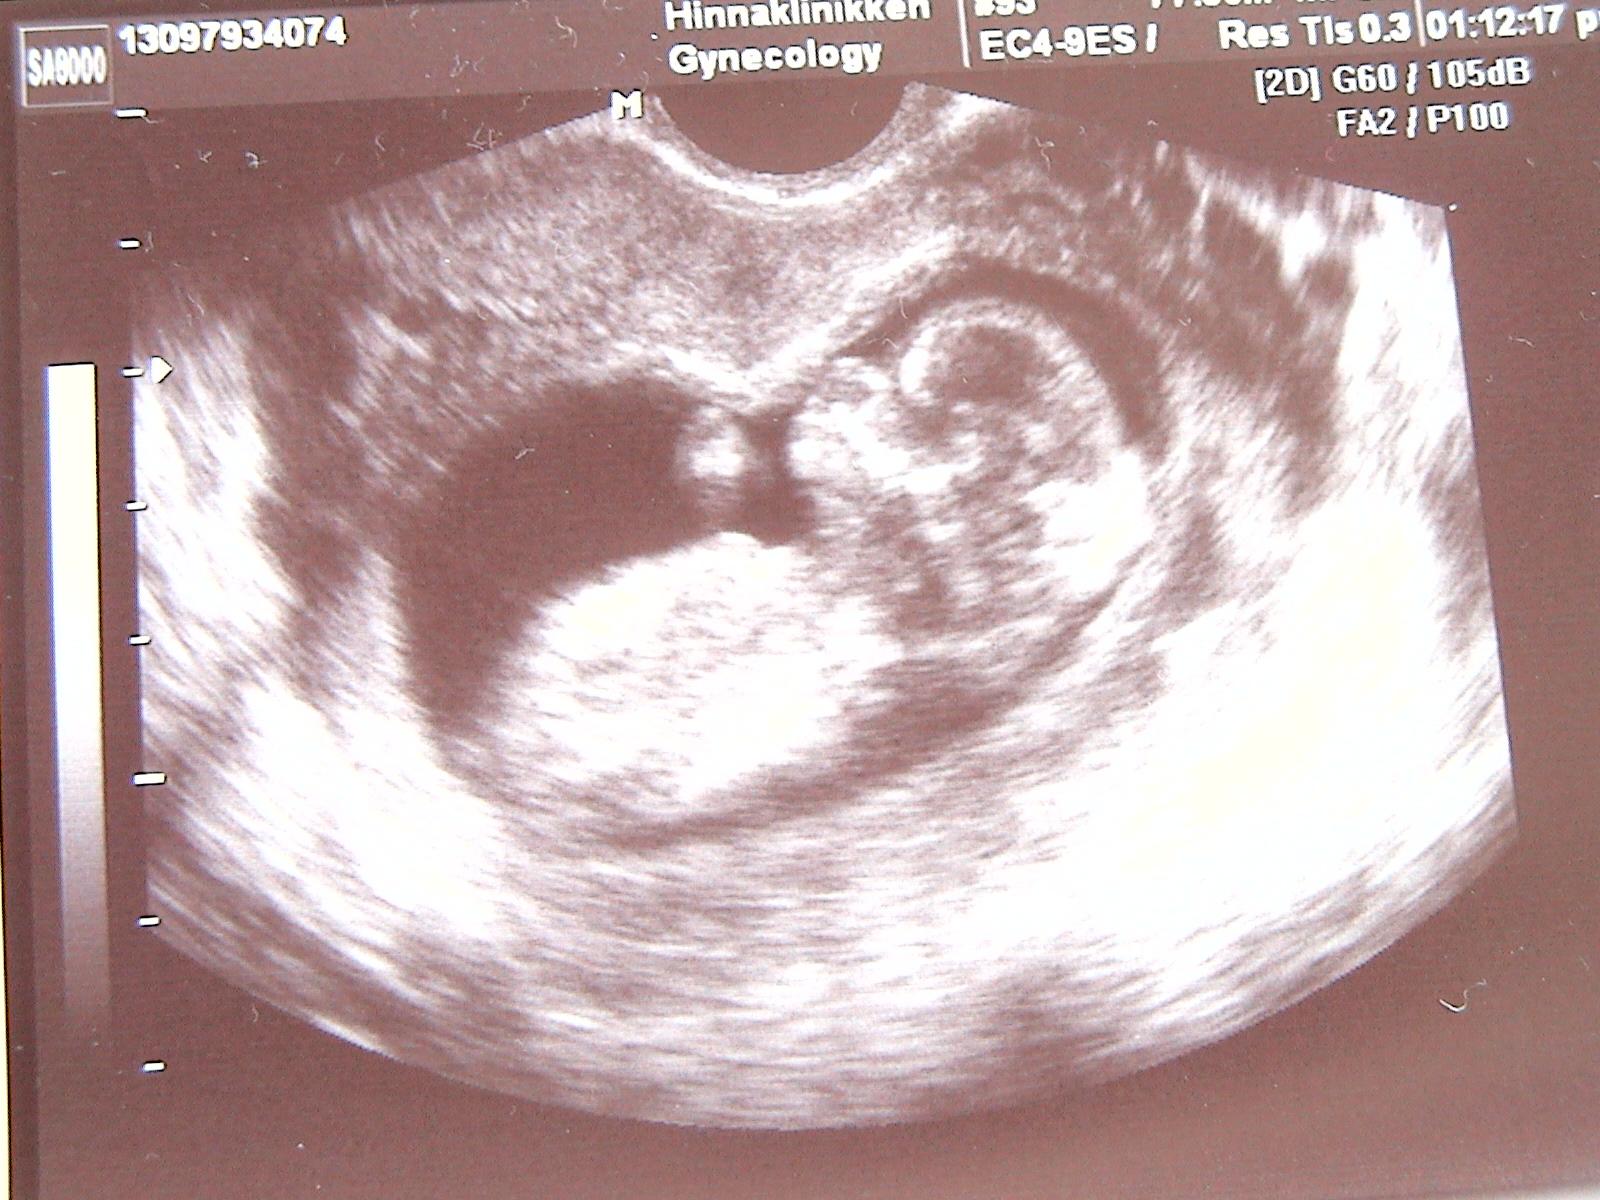

LilleLotte Skrevet 21. august 2006 Forfatter #24 Skrevet 21. august 2006 (endret) Da har jeg vært på ul. Alt så fint ut, var en baby i magen min. Så nå kan mannen slappe av og ikke tenke på å måtte kjøpe ny bil for å få plass til alle Lengden var 5,6 cm, hjerteslagene var 154 slag i min og alt annet så fint ut som sagt. Så nå gleder jeg meg til å komme på den ordinære ul i uke 17-20 for å få vite kjønnet. Glemte jo å si at jeg fikk termin 4 mars 2007. Endret 22. august 2006 av LilleLotte